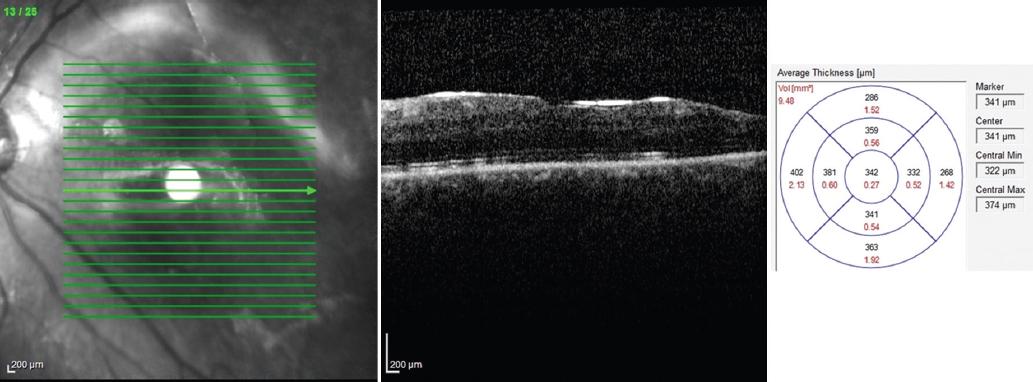

A partir de la primera semana de seguimiento se tomaron fotografías clínicas de fondo de ojo con una cámara TRC-NW7SF Mark II (Topcon Medical Systems, Inc., Paramus, NJ, USA). Se realizó una tomografía de coherencia óptica de dominio espectral (SD-OCT) (Heidelberg Engineering, Heidelberg, Alemania) de mácula para determinar la presencia o ausencia de membranas, pliegues y líquido subretiniano persistente e imágenes multicolor. El grosor foveal central fue determinado por algoritmos automatizados incorporados en el software de la SD-OCT Heidelberg (Figs. 1 a 4).

Figura 2 Imagen superior izquierda: tomografía de coherencia óptica de mácula a los 6 meses de la intervención quirúrgica. Se observa un grosor macular central de 307 μm. Imagen multicolor inferior: retina aplicada.

Figura 4 Imagen de tomografía de coherencia óptica de mácula a los 3 meses de la intervención quirúrgica. Se observa un grosor macular central de 342 μm.